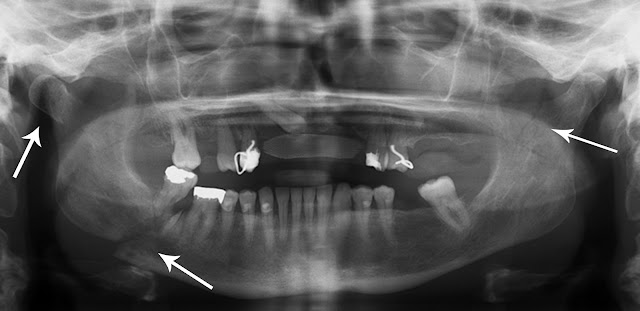

There area unit 2 styles of multiple fractures and these are: comminuted and segmental. basically, comminuted fractures area unit those whereby the fractures area unit placed quite near to one another, whereas the segmental fractures would happen once they area unit placed any aside from one another. the sort of multiple fractures will be diagnosed through varied advanced medical examinations. There will be multiple fractures of the pelvis, foot or perhaps multiple broken ribs. These will occur in kids or older alike.

Diagnosis of Multiple Bone Injuries

People could be questioning however multiple fractures will be diagnosed. As mentioned, this can be quite totally different from different styles of bone fractures in such some way that it's quite one harm space within the bone. To be ready to accurately verify the condition, it'll need the following:

4. Tomography